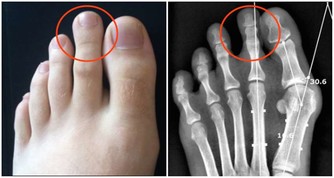

熱痙攣

通常發生在人進行劇烈運動目大量出時,人身體中的鹽分和水分隨汗液一同流失。肌肉中的含鹽量低可能是造成熱痙攣的原因。此外,停攣也可能是熱衰竭的一種表現。

1怎樣識別

表現為肌肉或抽描,發生在腰部手臂或部。常呈對稱性,時而發作。患者意識醒,體溫一般正常。

2怎樣處理

停止一切活動,靜坐在涼爽的地方休息;飲用稀釋、清爽的果汁或運動飲料;痙攣緩解後的幾小時內勿進行重體力勞動劇運動;如果病人有心髒病史、低鹽飲、小時後熱的狀況還沒有消退,要尋求專業的醫療處理。